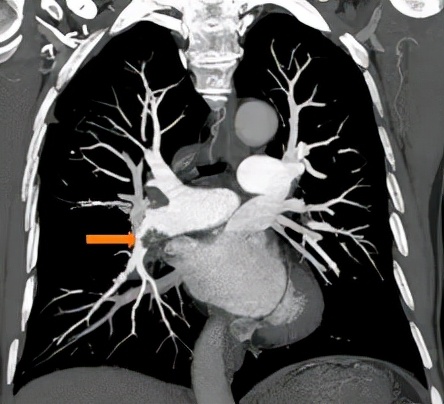

△肺动脉增强CT示:右下肺动脉主干及前基底段分支不完全性栓塞

除此之外,洪城副主任医师发现,梁伯肺部血管里面散布着 很多慢性血栓 ,考虑到他已经规范抗凝治疗三个月都还有这些血栓,初步判断为已经转化为慢性血栓,单纯的药物治疗显然已经不奏效了。

“我们发现他 双下肺、右上肺都有慢性血栓 ,如果不及时采取措施, 血栓一旦堵塞肺部的分支或主干道,形成肺栓塞,可能会引发严重后果,甚至会导致右心衰竭死亡 。”